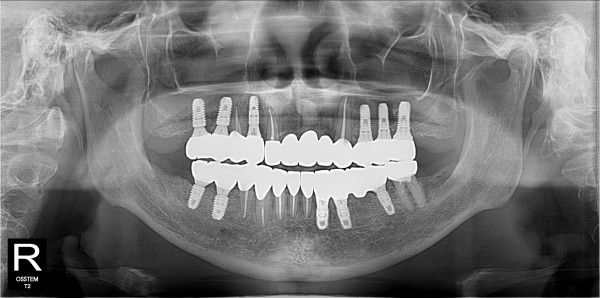

구치부 임플란트 최고관리자 0건 23-11-07 18:32 본문 구치부 임플란트 + 전치부 크라운 목록 이전글네비게이션 임플란트 23.11.07 다음글구치부 임플란트 23.11.07 댓글목록 0 댓글목록 등록된 댓글이 없습니다.